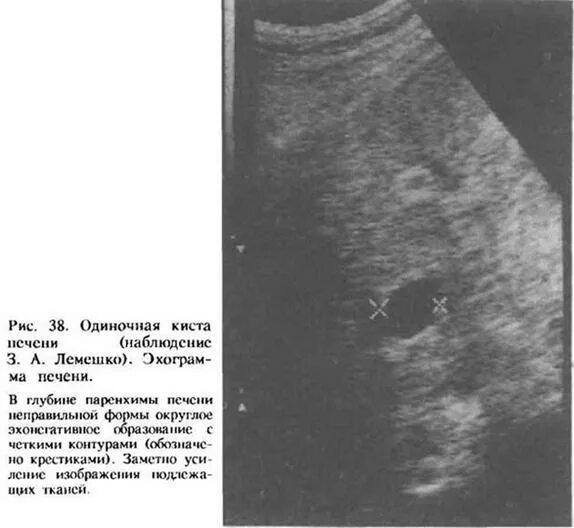

Метастазы в печени на узи как выглядят